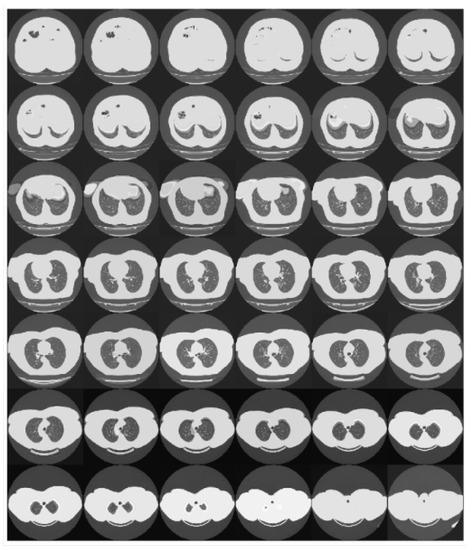

This pre-processing step has required to down-sample or over-sample the CT scans according to their original depth. The adopted strategy to perform these operations was to work at the ends of the scans, where generally, the information content is lower (see Figure 5). Basically, the oversampling was implemented by replicating the slices at both ends. Similarly, the downsampling was implemented by removing the slices starting from the ends.

Figure 5.

The figure shows the slices of a chest scan. It can be observed that the information content of the scan tends to reduce moving toward its ends.